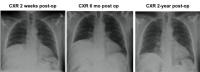

Following the surgery, the initial 2-week follow-up chest x-ray showed no change from baseline. The 6-month follow-up also showed no change from baseline. However, the 2-year follow-up chest x-ray showed the resolution of the patient's elevated hemidiaphragm. Additionally, the patient's exertional dyspnea was resolved by the 2-year follow-up visit. Dr. Winfree shares, "This was our first patient with Parsonage-Turner syndrome with hourglass constriction that we treated in our Diaphragm Paralysis Center. We look forward to reporting on additional patients as 2-year follow-up data becomes available.